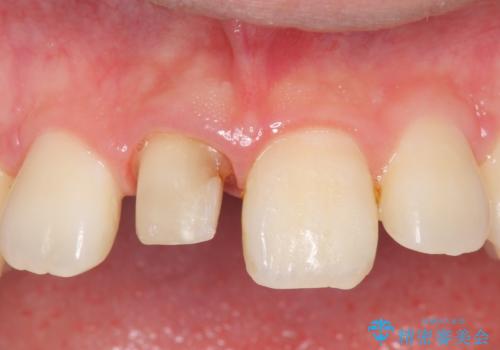

- 右上1番目の前歯の変色が気になるといらっしゃった方の症例です。

再根管治療後、オールセラミッククラウンによる補綴を行いました。